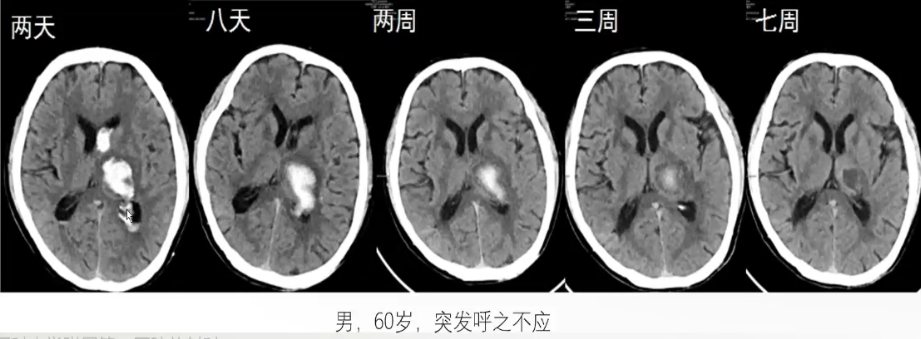

丘脑出血

❖ 丘脑出血发病平均年龄在60岁以上,以高龄、高血压、脑动脉硬化及活动或激动为主要的病因和诱因。

❖ 金以丘脑穿通动脉破裂出血最常见。临床上多突然起病,发展迅速,有不同程度的意识障碍及头痛、呕吐等颅压增高表现,临床症状主要取决于出血是局限于丘脑,还是向周围临近区域扩展及与出血量的多少。

CT表现:

急性期丘脑血肿常表现为丘脑内圆形、类圆形或不规则形高密度影,边界清楚或边缘可见窄带样低密度影围绕,邻近结构(如内囊、侧脑室三角区、第三脑室)可见不同程度的受压变形。由于丘脑血肿邻近第三脑室与侧脑室,故常可见丘脑血肿从邻近脑室缘破入侧脑室或第三脑室。